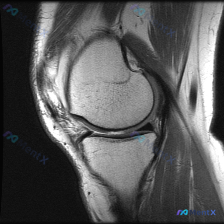

刚整理了一个很有临床意义的病例,核心矛盾是「临床怀疑软骨异常,但现有影像完全正常」,把整个分析思路分享给大家。 病例基础信息 这是一份单张膝关节矢状位T1加权MRI影像,临床提出的核心观察方向是「软骨异常」,无其他临床病史、症状或其他检查资料。 影像具体观察结果 我们先把影像所见说清楚: 1. 骨骼...

看到这个病例挺有代表性的,整理出来和大家分享一下思路。 病例基础信息 这是一张膝关节矢状位T1加权序列MRI影像,用户提出问题:观察图像是否存在软骨异常。 先给大家整理影像评估的基本结果: 1. 骨骼结构:股骨远端、胫骨近端、髌骨皮质连续,骨髓信号未见异常高低信号,关节面形态基本正常 2. 半月板:...

今天整理了一个很有启发意义的读片病例,问题是临床怀疑膝关节软骨异常,只给了一张矢状位T1加权MRI,我们一起来梳理整个分析过程。 病例影像基础信息 这是一张膝关节矢状位T1加权像(T1WI),我们先把基础解剖评估说清楚: 1. 骨骼结构:股骨远端、胫骨近端骨皮质连续,无骨质破坏或骨折,关节间隙正常,...

病例基础信息 这是一份特殊的膝关节影像评估需求:输入描述提示存在软骨异常 (Chondral abnormality),提供1张膝关节矢状位MRI静态图像,我们先看影像学分析结果: 影像学观察结果 1. 骨骼与软骨:股骨远端、胫骨近端、髌骨骨皮质完整,无骨折,无骨髓水肿;股骨髁、胫骨平台、髌股关节面...

病例读片讨论:怀疑软骨异常,单张MRI却没发现问题,该怎么办? 这是一份膝关节矢状位T1加权MRI读片需求,核心疑问是排查软骨异常,我整理了完整的分析思路分享给大家。 一、影像基础信息 本次读片仅提供单张膝关节矢状位T1加权MRI图像: - T1序列中,骨髓脂肪呈高信号,液体、皮质骨、半月板等致密组...

拿到这个病例:核心问题是「这张膝关节MRI里的软骨异常在哪里?」,先把读片结果和思路整理给大家。 一、先整理读片基本信息 这是一张单张膝关节矢状位MRI,信号对比度提示更符合质子密度加权像(PDWI)或T2加权像(T2WI),不是典型T1加权像,层面在膝关节中线附近,可以清晰显示后交叉韧带。 逐结构...